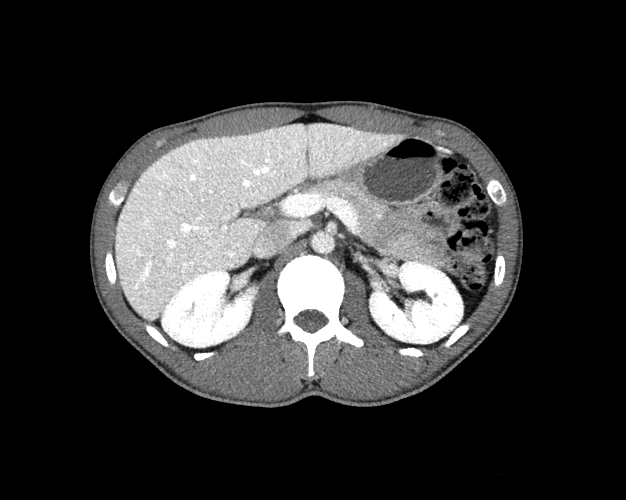

Body

Covers abdominal CT anatomy.